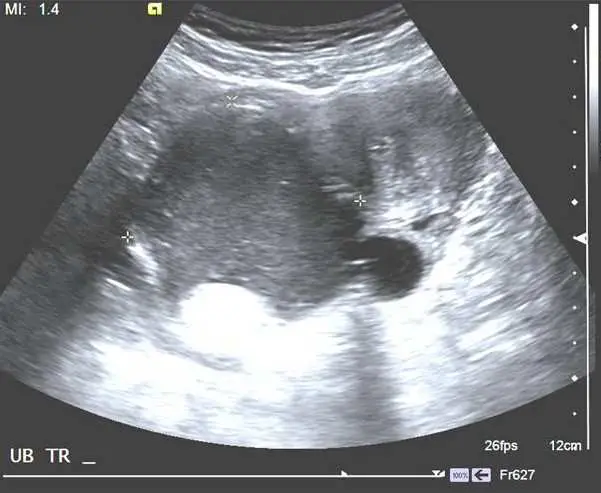

43 歲女性病人,健檢時發現 CA-199 升高,接受腹部影像檢查,上圖為骨盆處橫切超音波,下圖為 CT 最可能之診斷為何?

下圖:骨盆 CT(軸位切面)

CT 軸位像顯示骨盆腔中央有一個低密度(fat attenuation)的囊性病灶,白色箭頭指向其中一個結節狀的高密度鈣化灶(calcification / toot